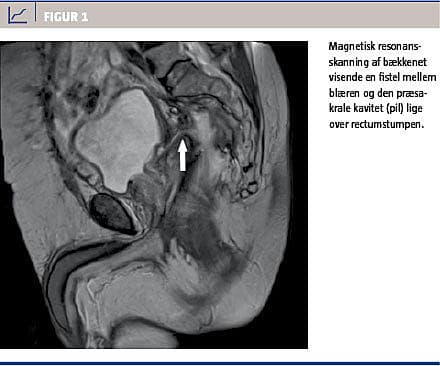

Tre et halvt år efter den primære operation havde patienten stadig mellem rectumstumpen og blæren en kavitet, der blev målt til 2,5 × 5 × 5,5 cm ved en kontrastindhældning i rectumstumpen. Der blev påbegyndt eVAC-behandling med skift hver 2.-3. dag. På dag 42 af behandlingen var der tegn på urinvejsinfektion og pneumaturi. Behandlingen blev stoppet, og ved en magnetisk resonans (MR)-skanning påviste man en fistel mellem den præsakrale kavitet og blæren (Figur 1). Dette fund blev bekræftet ved en cystoskopi. Patienten havde flere episoder med urinvejsinfektioner og blev behandlet med perorale antibiotika uden yderligere komplikationer. Der blev ikke konstateret lokalrecidiv.